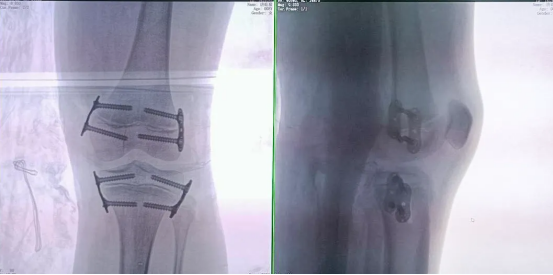

During the procedure, the positioning guidewire is inserted into the growth plate. A 3D scan is then performed by the 3D C-arm to confirm the guidewire's placement. Once verified, the plate is attached and secured with cannulated screws.

A final C-arm fluoroscopy check showed satisfactory positioning of the “eight-Plate” and proper screw direction. The wound was irrigated with saline, sutured, dressed, and immobilized with a brace, marking the completion of the procedure.